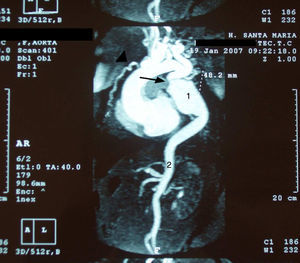

Over the course of three years, several computed tomography (CT) scans were performed, which showed no progression of the aneurysm (Figure 1).

MRI angiography disclosed a thoracic aortic coarctation with large poststenotic dilation (7cm long, 4.8cm maximum diameter), hypoplastic abdominal aorta and collateral circulation via the left subclavian artery and internal mammary artery (Figure 3).